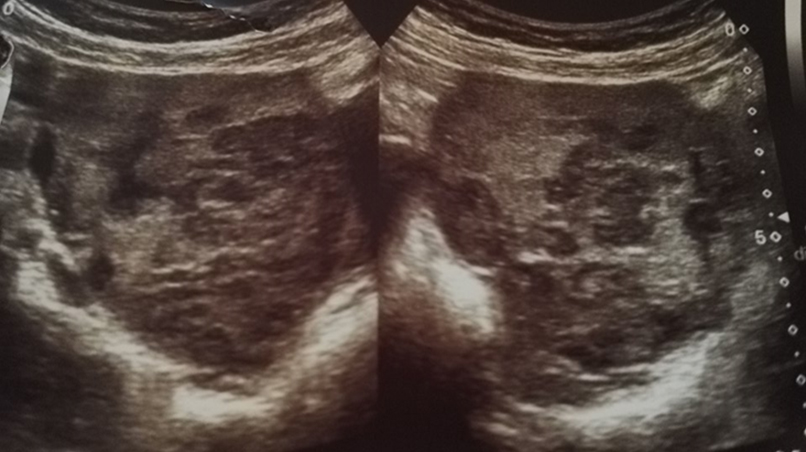

A 52-year-old menopausal woman who was referred for a palpable right adnexal mass detected on routine vaginal examination. A transvaginal scan revealed a right adnexal complex mass of mixed echogenicity measuring 6.6×5.7×8 cm (Figure 1), (Figure 2) with increased vascularity on colour doppler (Figure 3). The patient had no medical or surgical history of note.

Figure 1: Right adnexal mass of mixed echogenicity on transvaginal scan.

Figure 2: Heterogenic mass consisting of cystic and solid components on transvaginal scan.